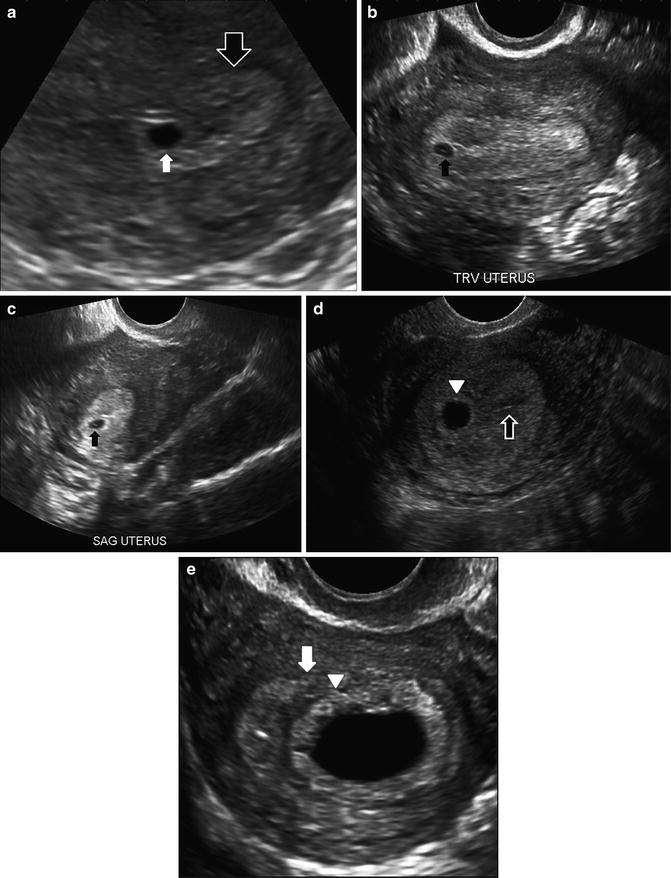

The gestational sac can be seen transvaginally as early as 4 weeks gestation when its greater diameter is 2 mm with corresponding human chorionic gonadotropin hCG levels around 1000 mIUmL International Reference Preparation or IRP. Its mean diameter bears a linear relationship with GA and increases 1012 mmday until the appearance of the fetal pole with its. Some parents believe that if the gestational sac is sausage-like it will be a baby boy.

If it is oval in shape it will be a baby girl. This is not true. The gestational sac GS is the first sign of early pregnancy on ultrasound and can be seen with endovaginal ultrasound at approximately 3-5 weeks gestation when the mean sac diameter MSD would approximately measure 2-3 mm in diameter.

A true gestational sac can be distinguished from a pseudogestational sac by noting. Sac shape gender prediction. Discussion in Pregnancy - First Trimester started by Mummy2aStar Sep 23 2013.

I had to ovals in my early scan and had girls. The appearance of a normal gestational sac. Is round or elliptical.

Is located in the upper body of the uterus called the fundus. Contains a smaller sac called the yolk sac. Contains the amniotic sac which will eventually take up the entire sac The appearance of an irregular gestational sac.

At 6w1d we saw a IU gestational sac size on target for GA a yolk sac of perfect shape. An irregular gestational sac as the name suggests is a gestational sac which does not have the well defined regular borders of a normal gestational sac. It is an imaging feature related to a non-viable pregnancy.

The gestational sac is the structure surrounding the fetus early in pregnancy and its shape early in pregnancy usually before 8-10 weeks is important. Ideally the gestational sac should be round. But other shapes can also be normal and there is no sure way of predicting what it means.

To develop a quantitative method for characterizing gestational sac shape. Twenty first-trimester gestational sacs in normal pregnancies were studied with three-dimensional 3D ultrasonography. The 3D coordinates of surface-point sets were obtained for each sac using 30- 15- and six-slice sampling.